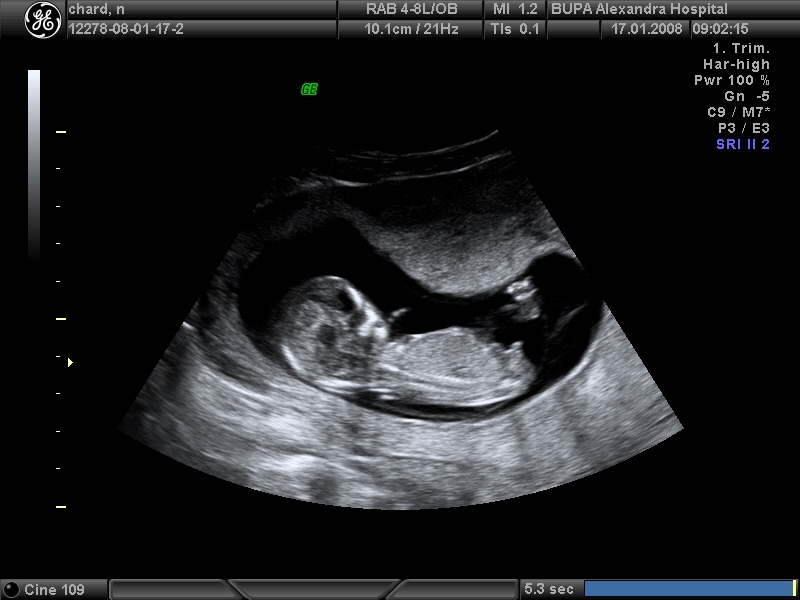

But here are some examples of what I mean with the different "types":

Attachment 26755

Attachment 26756

Attachment 26757

Attachment 26758

Attachment 26759